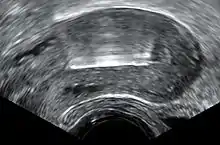

![]() Photo of a common IUD (Paragard T 380A) | |